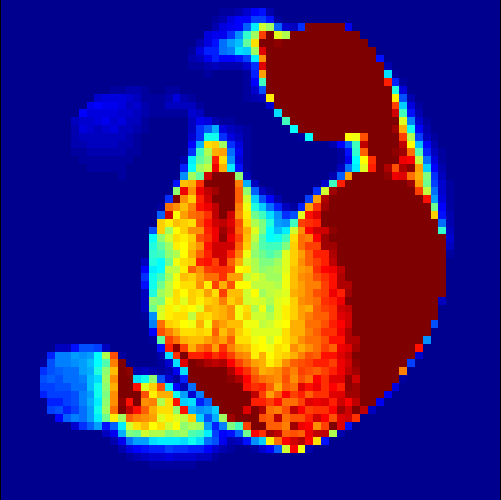

The parameters , and were optimized by comparing the final results with the existing ground truth in both cases. Here we mention that the choice of parameters is not a trivial task, since the result strongly varies with a change in the parameters. In figure 5, the scaling between the error in the -norm between exact and reconstructed image sequence per pixel per time step and the choice of each parameter out of a certain range is displayed examplarily for the heart data set. Here, we chose , and and kept two parameters fixed while plotting the error in the third one. The adaption of parameters in case of real data and, if possible, the elimination of some of them remains a future task.